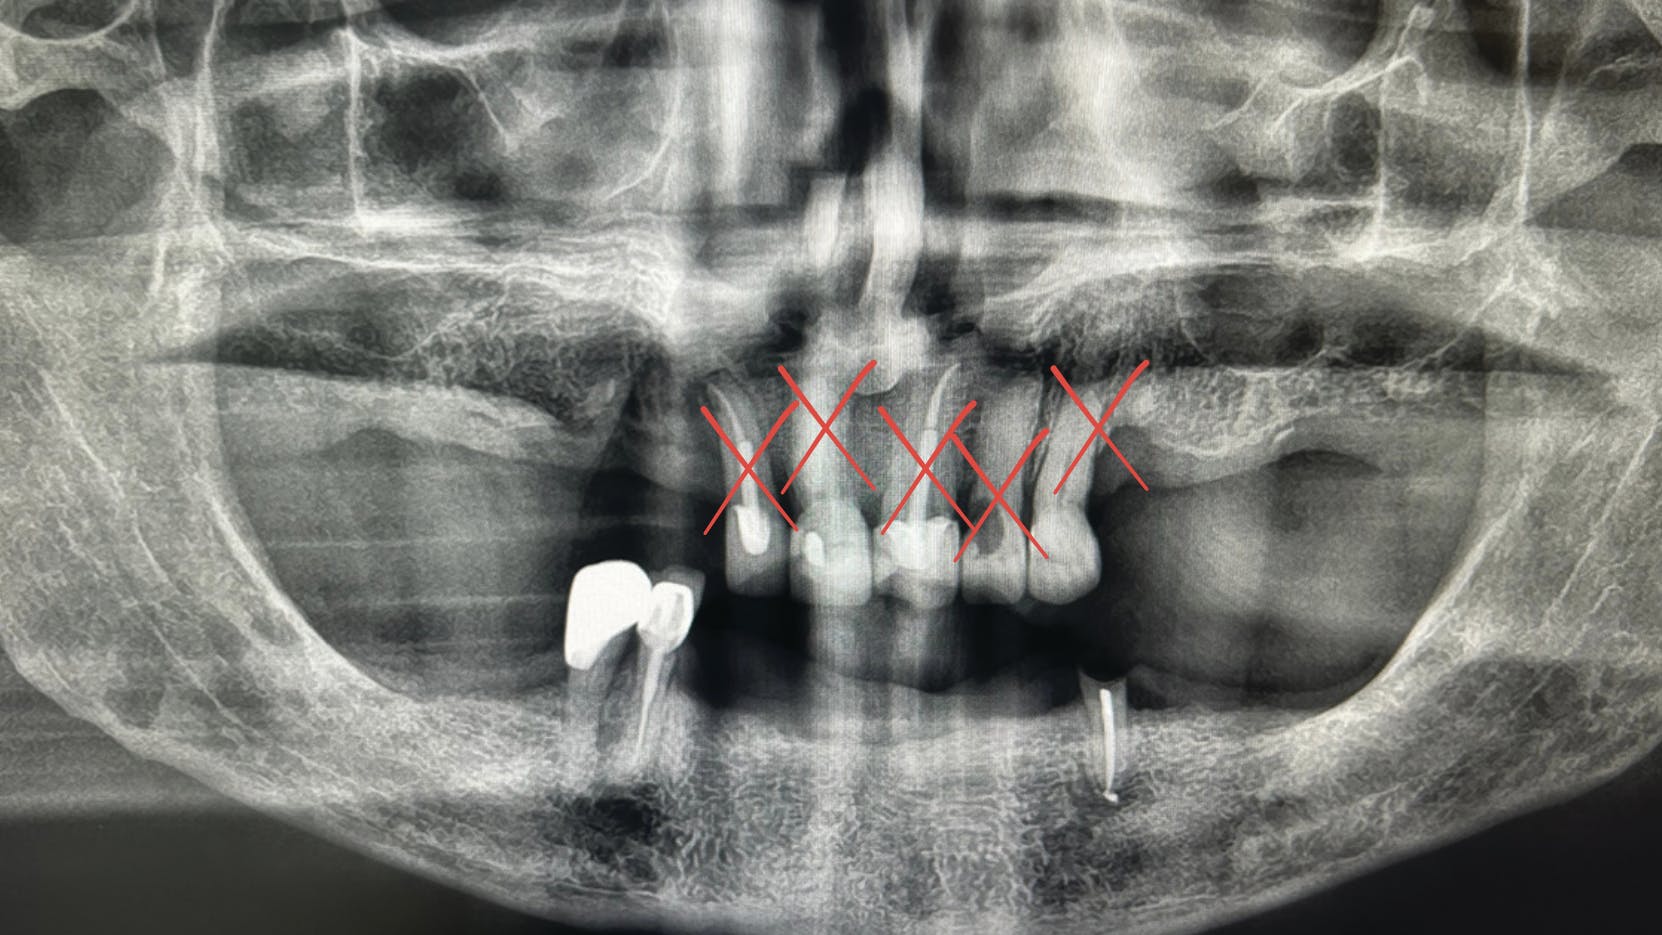

Adisak Riwkratok / Shutterstock.com

illustration of a tooth

Accurate staging and grading of periodontitis depends on correct use of clinical attachment level (CAL). This article clarifies common misconceptions, highlights pitfalls in probing...